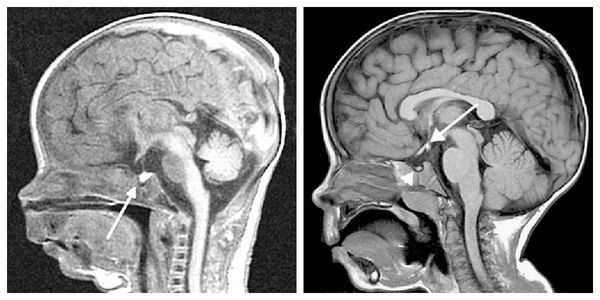

При необходимости проводится МРТ головного мозга и гипофиза с контрастированием [6] . Она позволяет исключить или подтвердить наличие объёмных образований области гипофиза и головного мозга.

Кроме исследования показателей гормонального профиля, оценки костного возраста ребенку проводится МРТ головного мозга. В случаях подозрения на врожденный характер заболевания показано проведение молекулярно-генетического исследования с целью поиска мутаций в генах.